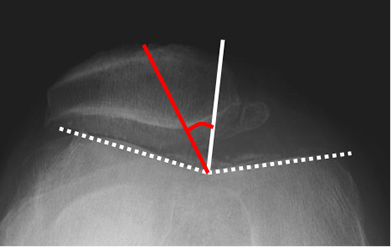

Fig 163. Inestabilidad patelar transversal.

Rx tangencial de patela. Angulo de congruencia positivo, por subluxación.